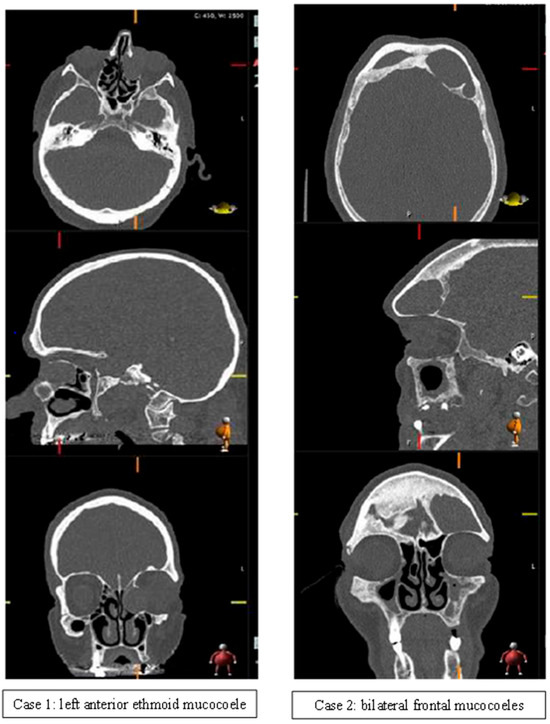

| Frontal | 14 (31) | 7 (47) | |